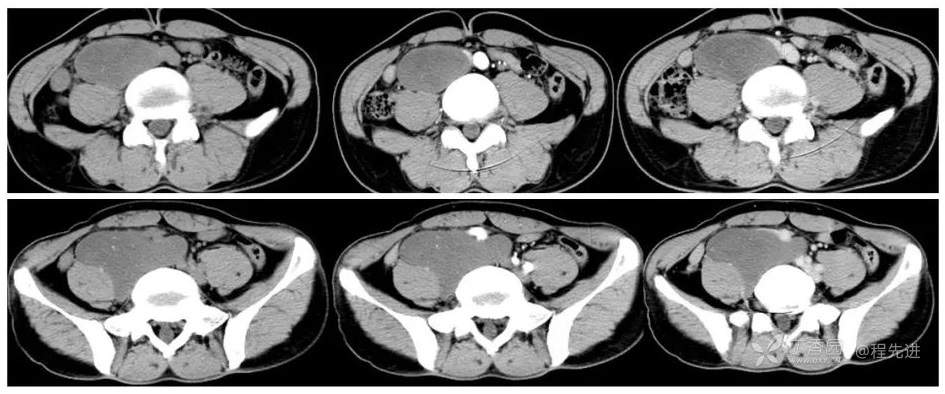

CT

从左到右依次是平扫、动脉期、静脉期

冠状位重建